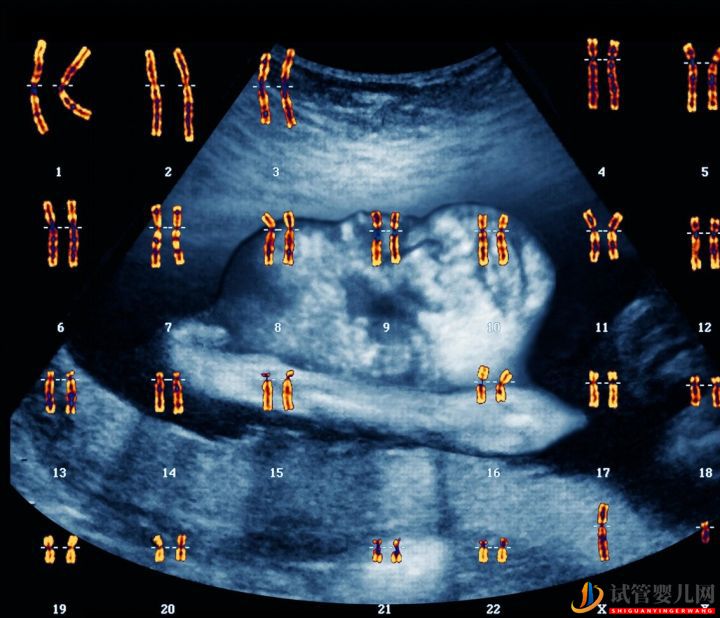

染色體的問題,染色體里記錄了胎兒發(fā)育必需的基本信息,它一旦出問題就容易造成流產(chǎn)。 染色體有問題的情況并不少見,據(jù)統(tǒng)計(jì)約 20%~55% 的早期流產(chǎn)是由于胚胎染色體異常。 染色體問題是導(dǎo)致很多女性流產(chǎn)和胚停的明確原因,所以在生殖中心就診時(shí)往往要查染色體。

在早期自然流產(chǎn)中,約50~60%與胚胎染色體異常有關(guān)系。染色體異常包括數(shù)目異常和結(jié)構(gòu)異常,前者以三體多見,常見的有,13-三體,16-三體,18-三體,21-三體,22-三體,其次為x單體;后者主要有平衡易位,倒置,缺失,重疊,嵌合體等。

有過不良妊娠史的,懷過染色體異常胎兒,21三體,X單體,夫妻雙方基本的檢查是染色體檢查。高分辨率的染色體核型檢查,可以檢查出羅氏易位、平衡易位、性染色體嵌合等染色體異常,這些異常增加了胎兒的三體等染色體異常的風(fēng)險(xiǎn)。